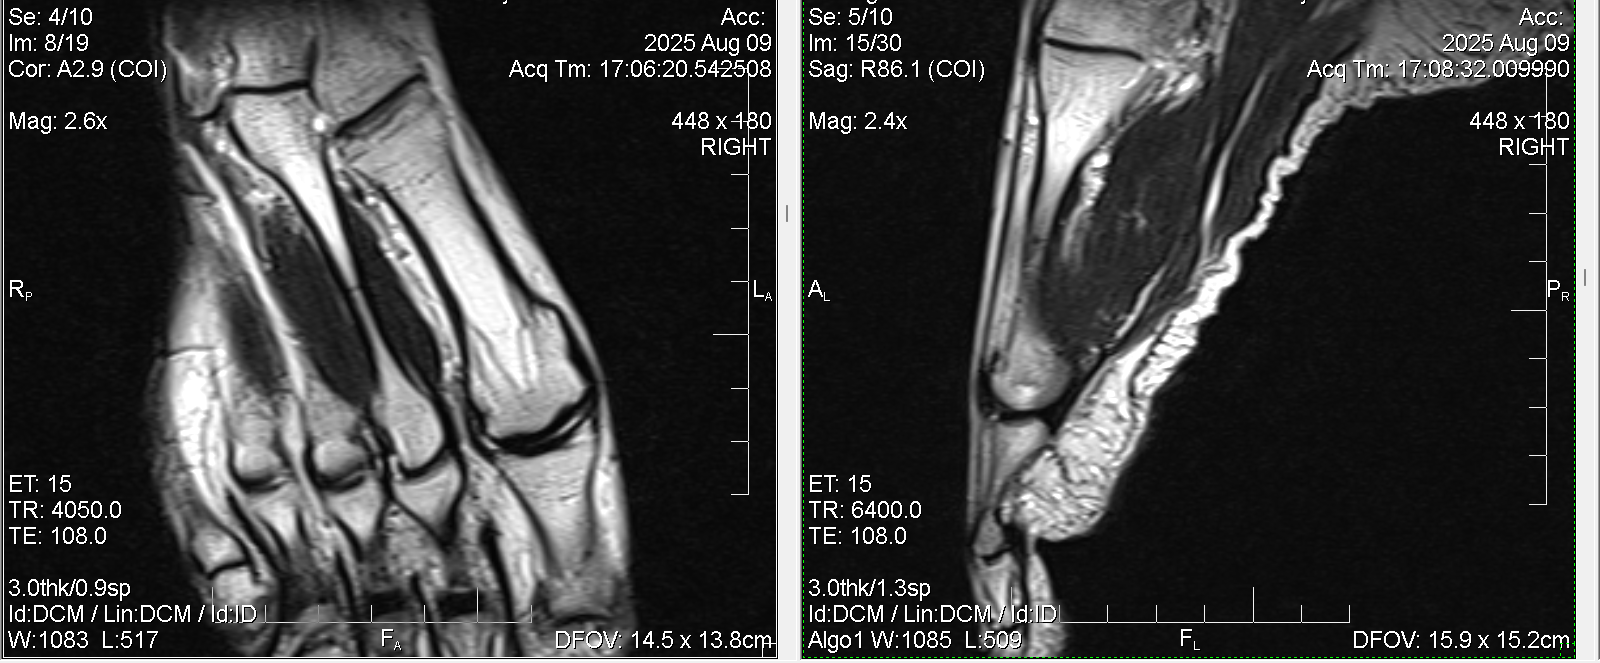

Нужна помощь рентгенологов. Есть ли на этом снимке перелом второй плюсневой кости ( маршевый или стресс)? МРТ Т2

След кард.

Примерно в этом месте сверху на коже покраснение.